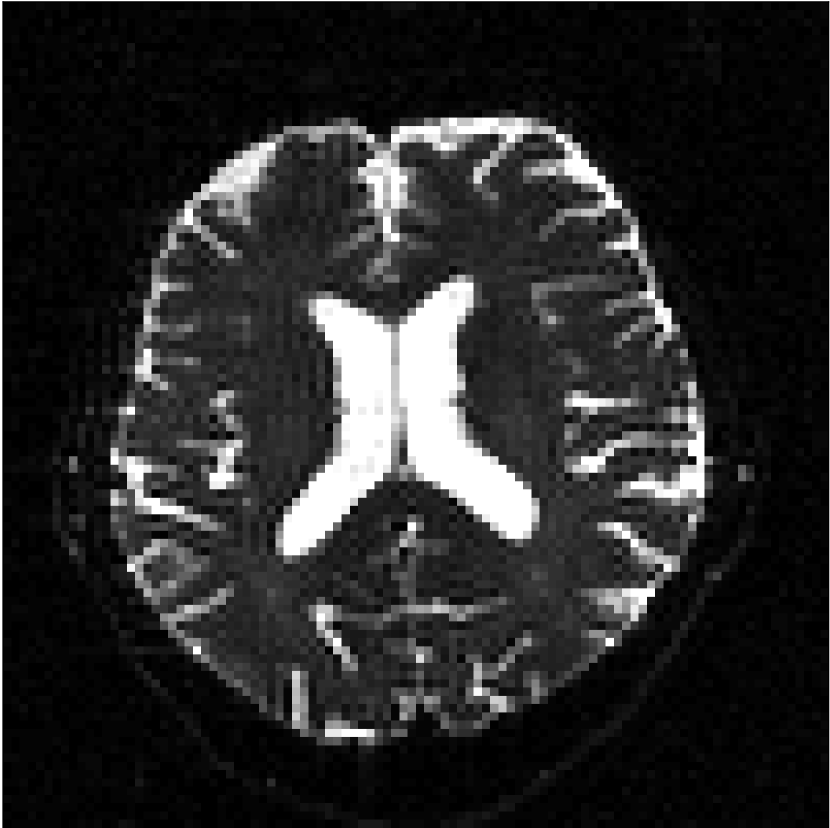

Figure 10 compares mean diffusivity maps across various partial Fourier factors between the CCNN and state-of-the-art methods.

No PF

7/8 PF

6/8 PF

5/8 PF

SoA

MD, m2/ms

CCNN

The methods perform similarly without partial Fourier acceleration, but as partial Fourier acceleration increases, the image is continually degraded in the SoA method, with "black voxels" appearing around the lateral ventricles. The CCNN method mitigates the appearance of these artifacts in the parameter maps.